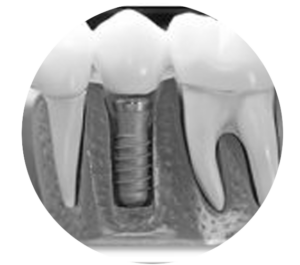

We are a full-service dentistry practice dedicated to meeting all your dental needs under one roof. From preventive care and routine checkups to cosmetic treatments and restorative procedures, we offer a wide range of services tailored to each patient. With advanced technology and a compassionate team led by Dr. Jenny Wilson, we ensure that every visit is comfortable, efficient, and focused on helping you achieve a healthy, beautiful smile.